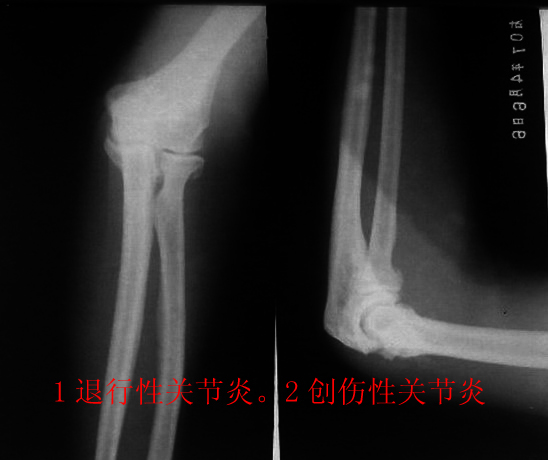

男性70岁。肘部跌伤2天。pe:肘关节肿胀,压痛(+)活动障碍。追问病史患者自诉以往关节稍肿胀,变形.

肘关节各关节面增生硬化,关节腔狭窄,考虑:1增生性关节炎。2创伤性关节炎。

肘关节骨关节炎,未见新鲜骨折

患者男.70岁.外伤2天,未见明显骨折时间短不考虑创伤性关节炎。考虑增生性关节炎.

上图片可能使用的是感兰片,需更换感绿片效果更好,图片清晰,信息量也多。收费可提高,对病人,对医院,对放射科医生都是有好处的。上图病例考虑肘关节骨关节病,桡骨小头是否有新鲜骨折,还需复查。